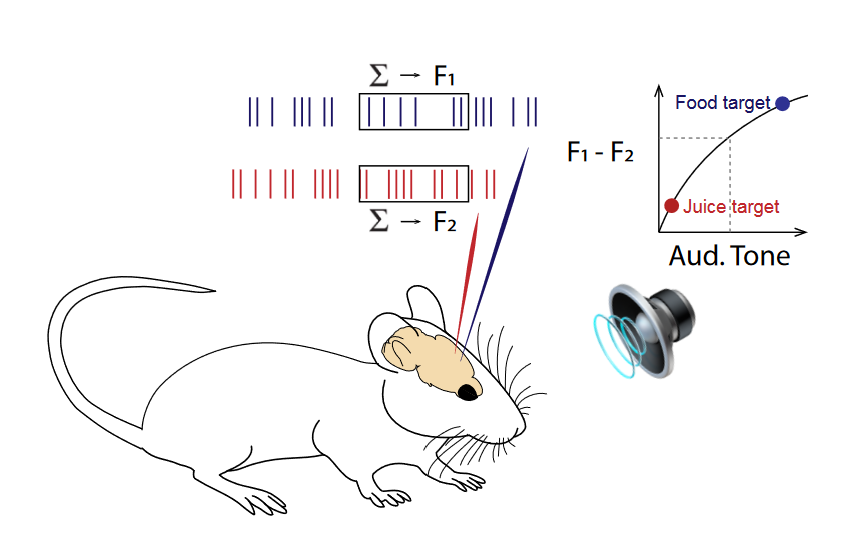

Thesis "Multiscale Modeling of Epileptic Seizure Dynamics" under the supervision of Viktor Jirsa (theoretical physics) and Christophe Bernard (neurophysiology).

- Delivered IBM Solutions in brain modeling to clients (CHDI, Pfizer) investigating Huntington’s disease phenotypes in-silico.

Check out some of my work